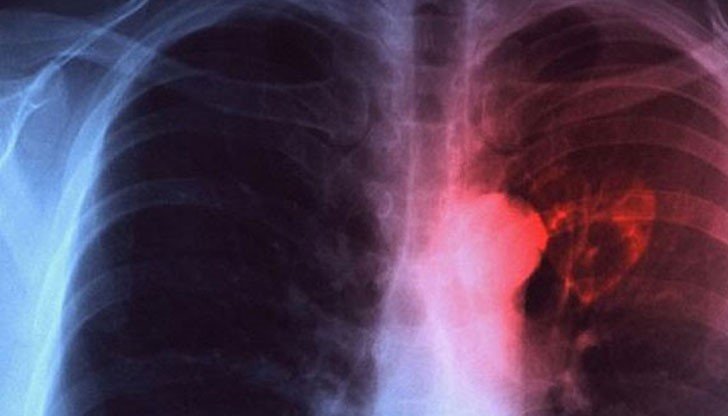

Туберкулозата остава глобален здравен риск. Много хора я свързват с миналото. Данните обаче показват друго. Смята се, че около една четвърт от населението по света е заразено с туберкулозната бактерия. При повечето хора болестта не се развива. Рискът обаче остава. Затова ранното откриване има значение.

В този контекст РЗИ и МБАЛ „Д-р Стамен Илиев“ в Монтана организират националната кампания „Седмица на отворените врати“ за туберкулоза. Инициативата е по повод Световния ден за борба с туберкулозата, който се отбелязва на 24 март.